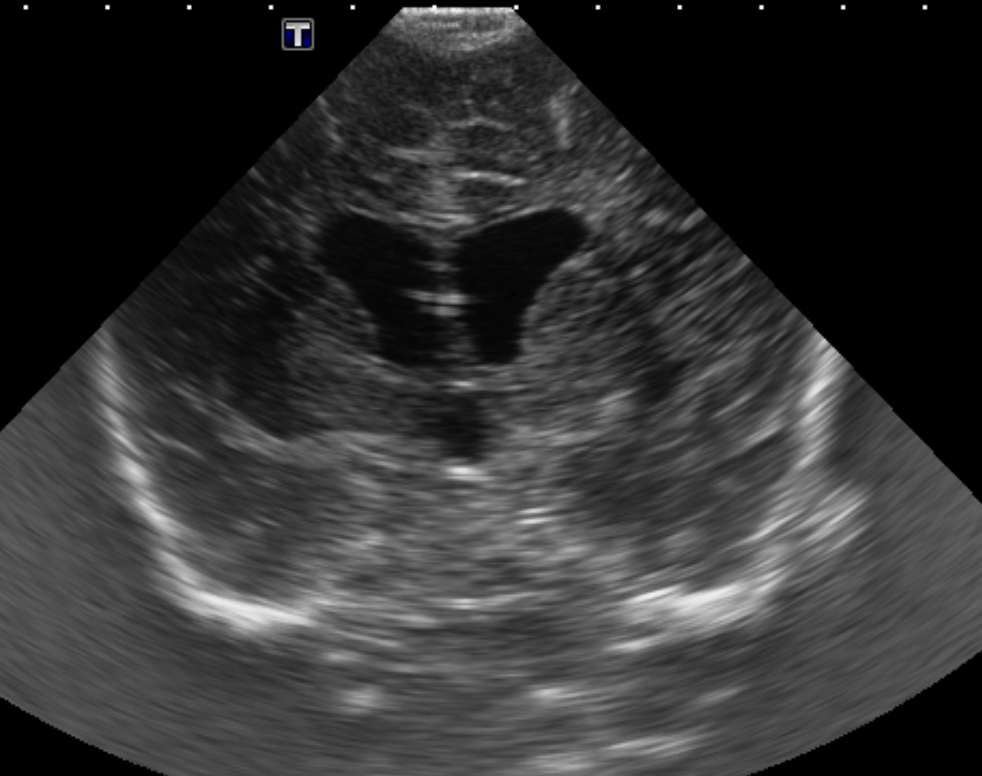

CSF spaces/ventricular system

There is prominence of the ventricular system. [Yes/No]

There is an asymmetry of the ventricular system. [Yes/No]

There is a cavum septum pellucidum. [Yes/No]

There is a midline shift towards right/left. [Yes/No]

The lateral ventricle/s are dilated. [Yes/No]

The third ventricle is dilated. [Yes/No]